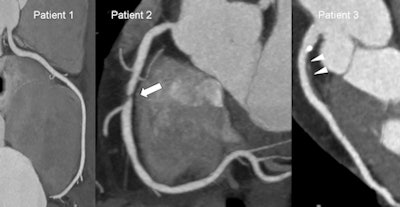

| Images show coronary CT angiograms of three different patients of similar age and with similar risk factor profiles. Images were acquired with a dual-source CT system (Siemens Flash; radiation dose <1.5 mSv for each patient). Patient 1 has normal coronary arteries. Patient 2 has a significant coronary stenosis in the absence of coronary calcifications (arrow). Patient 3 has a large soft plaque (arrowheads) and smaller calcified plaques in the absence of luminal narrowing. According to a recent meta-analysis by Bamberg et al, patients 2 and 3 have an increased risk of future cardiovascular events compared to patient 1, despite similarities of age and risk factor profile. Hazard ratio for patient 2 = 10.7; hazard ratio for patient 3 = 4.5. (Provided by Dr. Fabian Bamberg) |

Lowered radiation dose means that CT angiography (CTA) has become far more acceptable in intermediate-risk patients for assessing the future risk of a major cardiac event, such as myocardial infarction or the need of coronary stenting. CTA used to involve a dose of 10 to 20 mSv, but with the latest scanners, half of patients examined receive less than 1 mSv. Even scanners released in the past five years usually involve a dose of only 3 to 8 mSv. In addition, a recent meta-analysis has shown that the presence of ≥ 1 significant coronary stenosis was associated with an annualized event rate of 11.9%, with a corresponding hazard ratio of 10.74, demonstrating that coronary CTA can be used to identify patients at risk for cardiovascular events.

"Blooming artifacts due to extensive coronary calcifications may hide the extent of stenosis, but this can at least in part be compensated for with thinner slices and faster rotation," Reiser said.